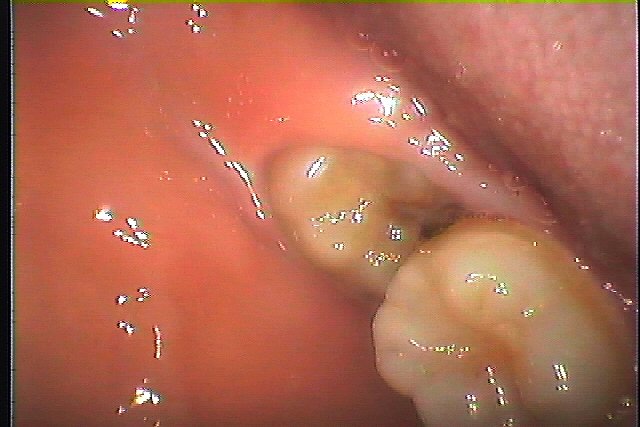

この親不知を抜歯していきます

一つ手前の歯にも重篤にもなりかねない虫歯を作っています

麻酔をかけて抜歯していきます